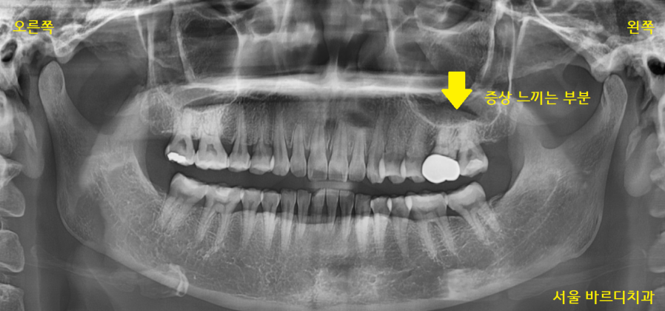

환자분이 처음 미사역 치과를 내원하셨을 때

왼쪽 위에 어금니가 불편하시다고 하셨습니다.

원인 파악을 위하여

x-ray를 찍어보았습니다.

230320 깨끗합니다.

특별히 뿌리에 염증이 있다거나

문제 있는 치아는 없었는데요.